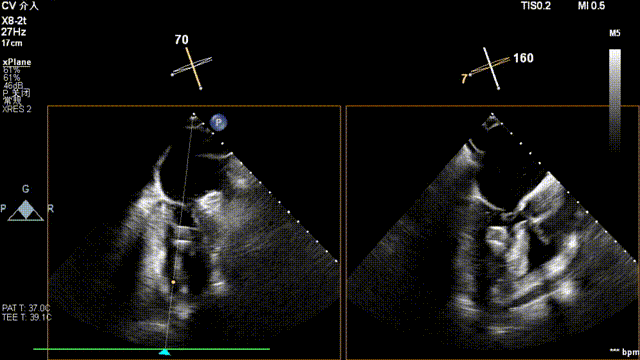

术后超声

最终在A3P2位置夹合,前叶夹合量10mm,后叶夹合量8mm,剩余瓣口面积3.45cm²,平均跨瓣压差2mmHg,反流基本消除。

术后30天